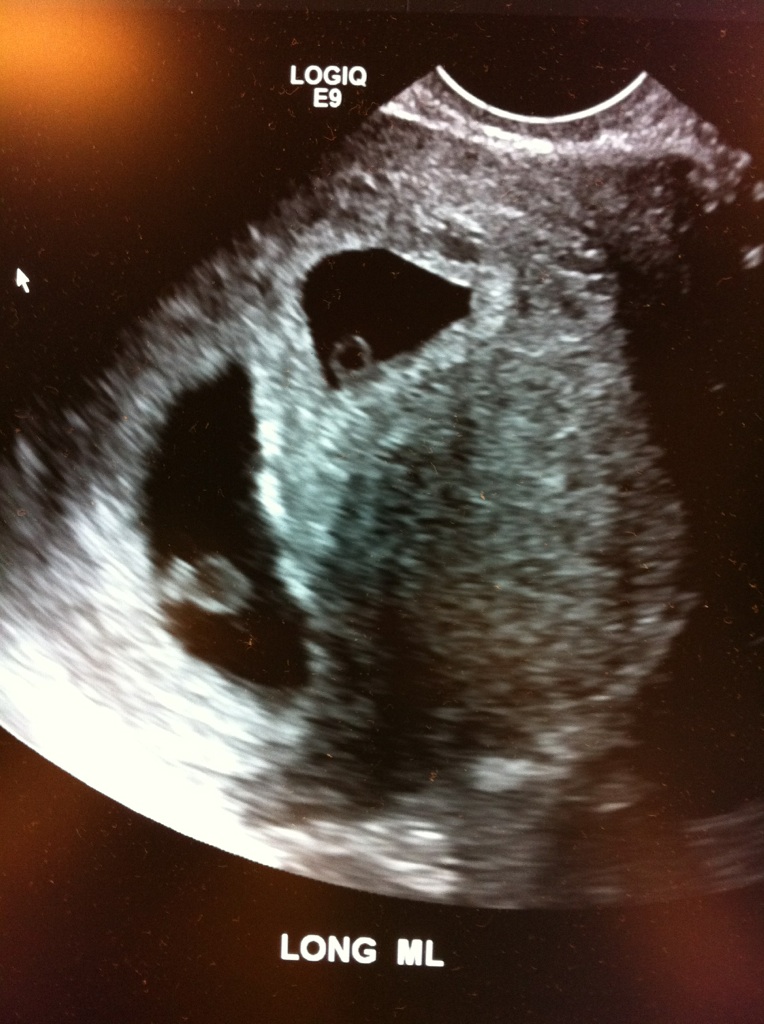

So yesterday we had a Dr. appointment and an ultrasound. And guess what? Those little babies are starting to have legs and arms! It was the most amazing thing to see them moving around in there, they are really starting to take shape! When we had the 7 week ultrasound (that Marisa posted pictures of) Marisa was 7 weeks pregnant - baby A was 6 weeks 6 days old and baby B was 7 weeks 1 day old. Yesterday Marisa was 9 weeks 1 day pregnant, and both baby A and B were 9 weeks day pregnant- so it looks like everyone is getting in sync with each other. They both had strong heartbeats of 176 BPM. Everyday I just become more and more amazed by these little babies! It brings a huge smile to my face just thinking about it! So here are the latest pics.

Below are the ultrasound pictures from yesterday and the video that Andrea took of one of their heartbeats.